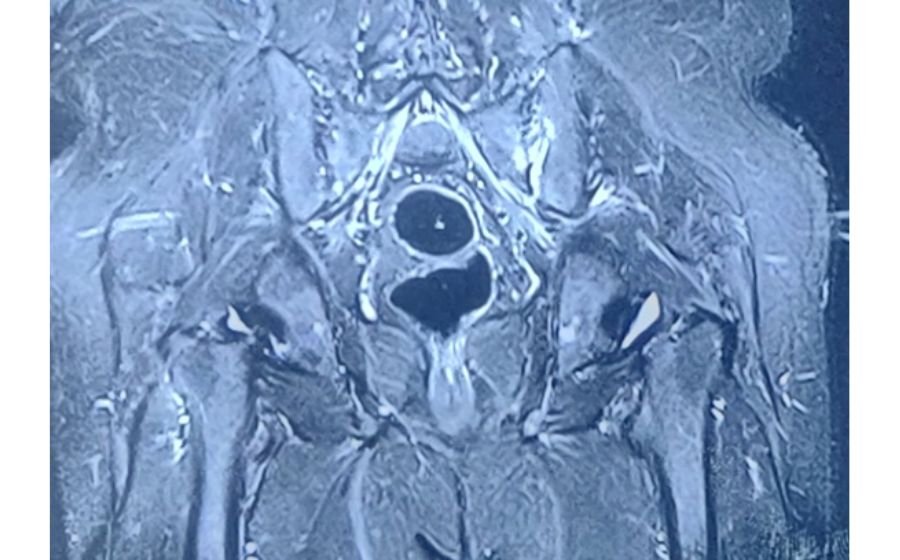

Cervical Myelopathy

Cervical myelopathy occurs when the spinal cord in the neck is compressed due to disc degeneration, ligament thickening, or arthritis. This pressure can cause imbalance, hand clumsiness, difficulty walking, and weakness in the arms or legs. Early diagnosis with MRI is crucial because symptoms can gradually worsen over time. Treatment focuses on decompressing the spinal cord—often through ACDF, cervical disc replacement, or posterior decompression—to prevent progression and improve function. Surgery aims to protect the spinal cord, restore stability, and enhance mobility and quality of life.